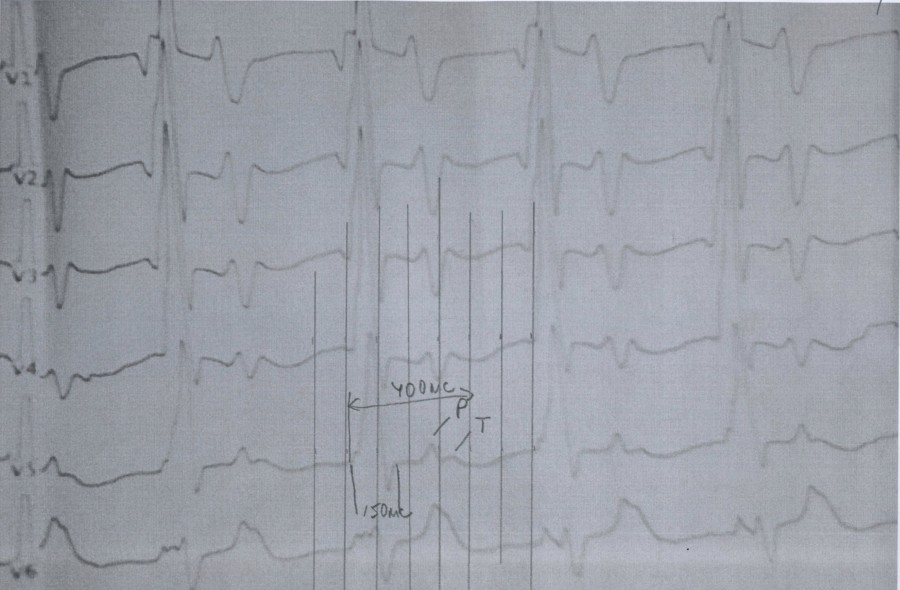

Анамнез - аномальное отхождение магистральных сосудов, сосуды из одного желудочка. Порок не коррегированный

Ритм АВ узла